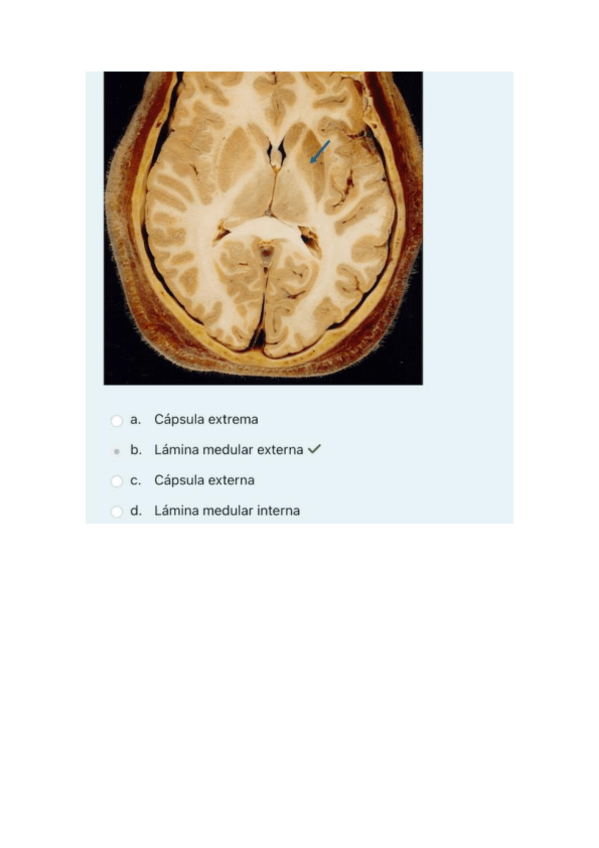

01.-Parcial-1-2023-teoria-resuelto.pdf

1o-parcial-practicas-2024-neuroanatomia-resuelto.pdf

1o-parcial-teoria-2024-neuro-resuelto.pdf

02.-Parcial-1-2023-practica-resuelto.pdf

2o-parcial-practicas-2024-neuroanatomia-resuelto.pdf

2o-parcial-teoria-2024-neuroanatomia-resuelto.pdf